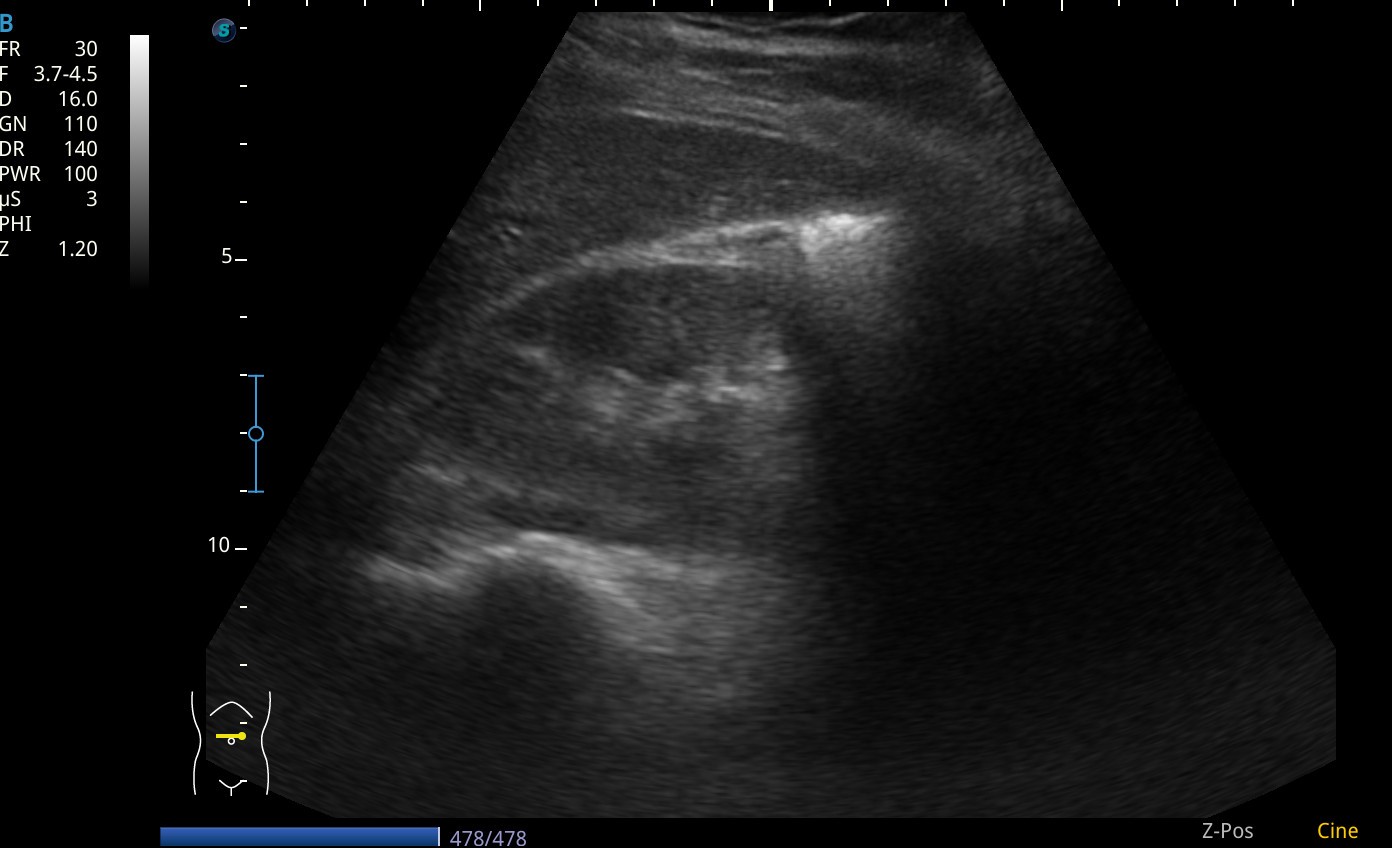

Se realiza ecografia a pie de cama que muestra como en el flanco derecho presenta silueta renal con un polo superior visible, sin poder definir el polo inferior, y la misma imagen en la silueta renal izquierda.

Asi mismo vemos a nivel de epigastrio bajo (zona umbilical), tejido sugestivo de parénquima renal que cruza por delante de grandes vasos, imagen compatible con un riñon en herradura.

En pelvis renal izquierda se aprecia una imagen hiperecogénica, sugestiva de microlitiasis.

El TAC abdominal confirmó la presencia de riñón en herradura, y de litiasis en la pelvis renal izquierda, sin otras anomalías morfológicas destacables.